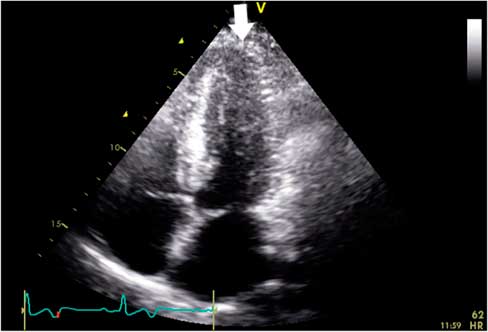

The patient was treated for an acute ST-elevation myocardial infarction (STEMI) in the ED and was later admitted to the coronary care unit (CCU) after the initial treatment. He was initiated on aspirin, clopidogrel, intravenous heparin infusion, and atorvastatin. As the patient presented to a non–percutaneous coronary intervention (PCI) capable hospital, the anticipated first medical contact to device time was >120 minutes; tenecteplase 50 mg was administered intravenously 60 minutes into his presentation. The patient was free of chest discomfort 90 minutes into admission. During admission, serial ECGs showed no resolution of the ST-segment elevation and persistent T-wave inversion (Figure 1). High-sensitivity cardiac troponin T was within normal limits, and both troponin and creatine kinase remained stable over several days. A coronary angiogram performed 13 hours into his presentation revealed normal coronary arteries without evidence of obstructive coronary disease with a left ventriculography demonstrating obliteration of the apical cavity at end-systole (Figure 2). Transthoracic echocardiography revealed a progressive increase in LV wall thickness toward the apex without evidence of LV systolic dysfunction or outflow tract obstruction (Figure 3). However, apical views were suboptimal, and no spade-like appearance of the apex was observed. On admission day three, the patient was discharged home on metoprolol.

Figure 3 Transthoracic echocardiography showing progressive increase in wall thickness toward the left ventricular apex (white arrow) in the apical four-chamber view